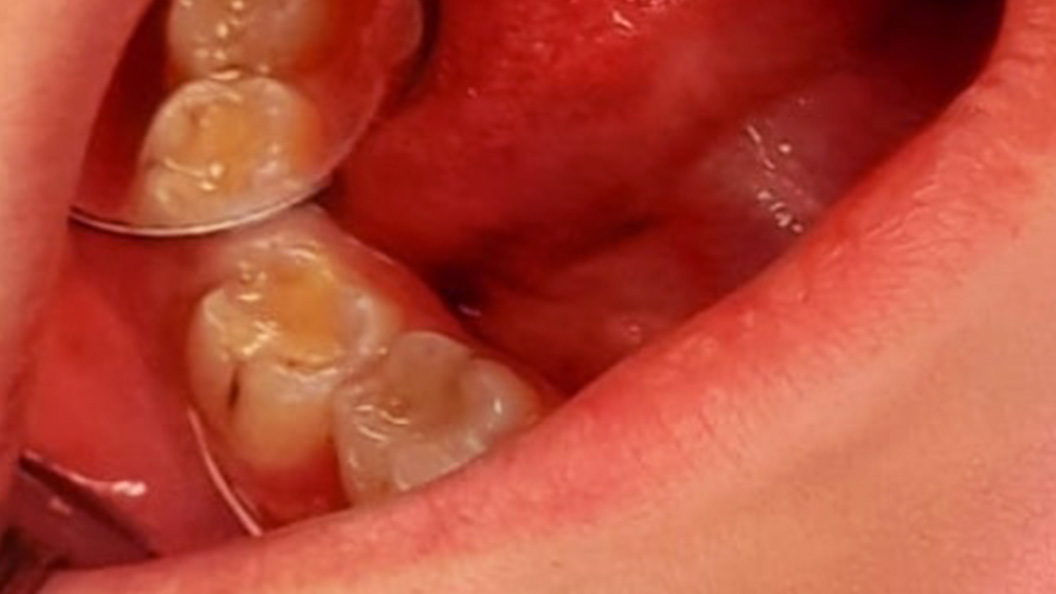

В клинику обратилась пациентка с жалобами на потемнение боковых зубов нижней челюсти, а также острую, быстро проходящую боль от холодного и шероховатость пломб. В процессе осмотра врач выявил глубокий кариес нижних моляров 4.6 и 4.7. Проведено лечение кариозных полостей с использованием композита светового отверждения Estelite.

Ход лечения:

- проведение местной анестезии;

- вскрытие, очищение и обработка кариозной полости;

- установка пломб из композита светового отверждения Estelite.